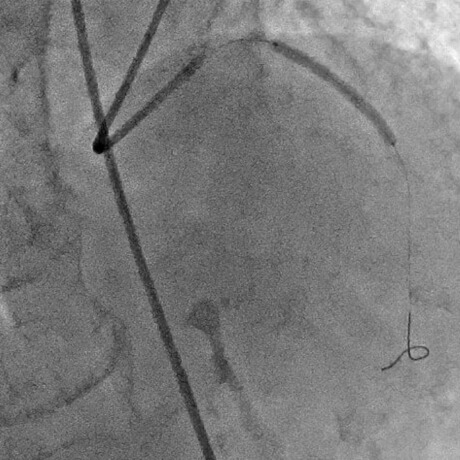

バルーンで閉塞部を拡張

血流は良好に改善したが、拡張は不十分